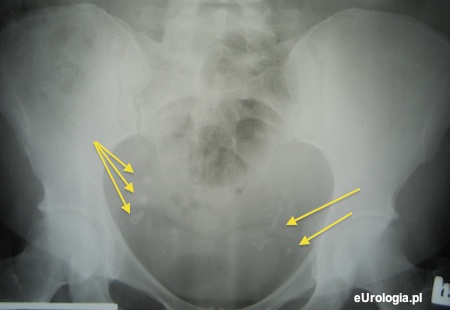

Flebolity są często spotykane na zdjęciach przeglądowych jamy brzusznej. Nazwa flebolit pochodzi od greckich określeń phlebos - żyła i lithos - kamień. W potocznym języku flebolity nazywane są kamieniami żylnymi i są niczym innych jak wysyconymi solami mineralnymi skrzeplinami w obrębie splotów żylnych miednicy. Flebolity nie wymagają żadnego leczenia i nie są niczym nieprawidłowym.

Fot. Bardzo liczne flebolty w miednicy małej.